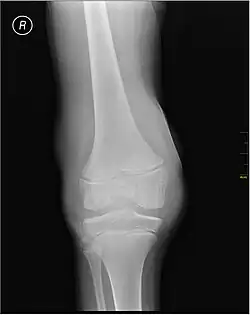

-

X-ray of Hemarthrosis -

X-ray of Hemarthrosis